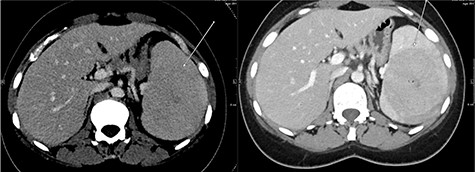

A repeat contrast-enhanced CT scan 21 months later showed an increase in size of the lesion to 8.0 × 7.2 × 6.6 cm (Fig. 4). Positron emission tomography (PET) CT demonstrated the mass to be moderately hypermetabolic with a standardized uptake value (SUV) of 4.7 (Fig. 5).

The post-contrast CT axial image showing central hypodense splenic lesion in portovenous phase (arrow—right image) which becomes isodense on delayed images (arrow—left image).